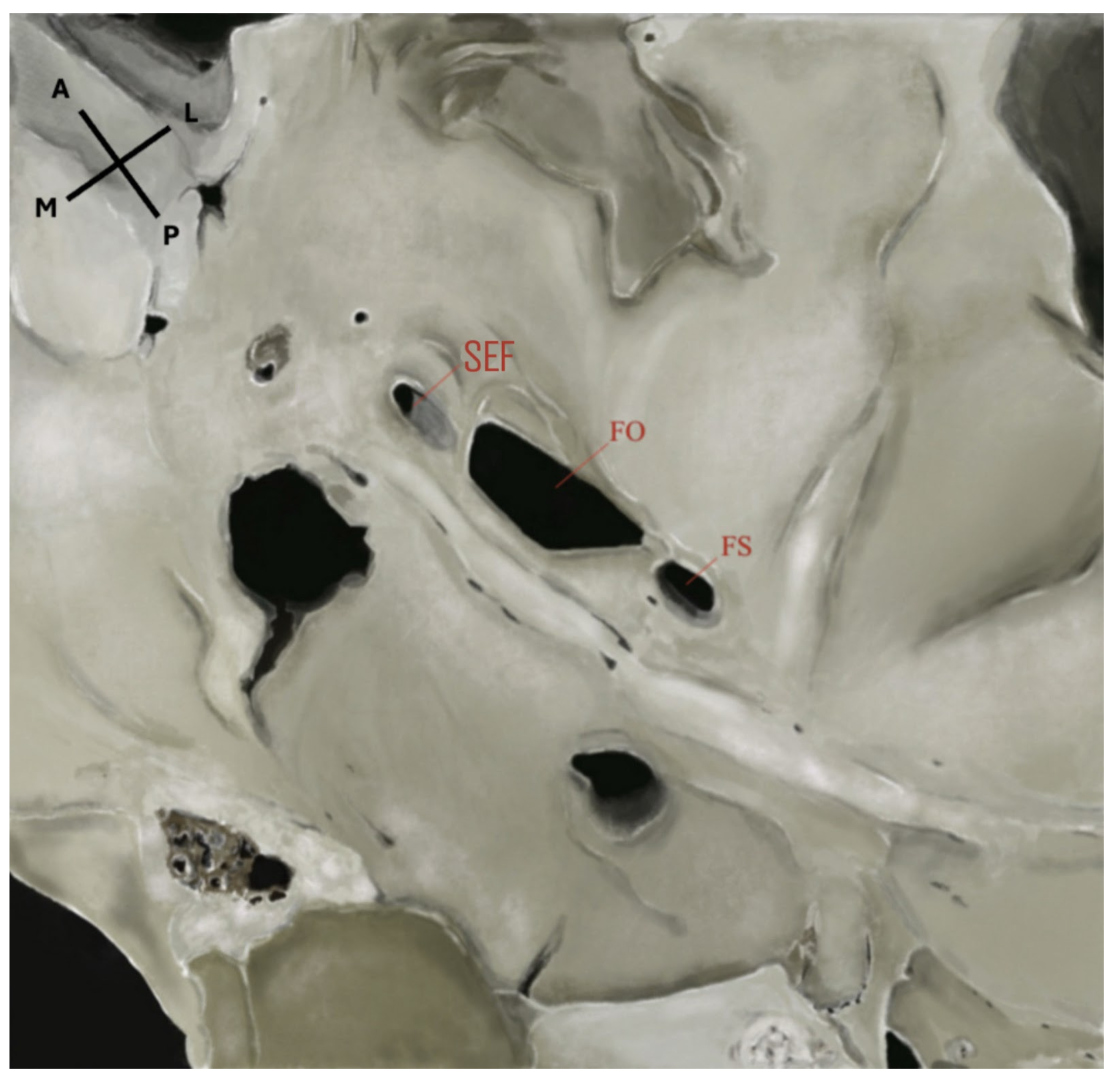

The sphenoidal emissary foramen (SEF)—also known as the foramen Vesalii or foramen venosum—is an inconstant and highly variable foramen situated in the greater sphenoidal wing within the MCF (Figure 1 and Figure 2). It is usually positioned anteromedially to the FO and FS, and posteromedially to the foramen rotundum (FR). Its extracranial aperture opens into the scaphoid fossa, located within the pterygoid process [6,7]. SEF may occur unilaterally or bilaterally and, although rare, may appear duplicated. When it forms a complete canal across the cranial base and remains patent, it becomes clinically significant, as it may transmit a venous channel between the pterygoid venous plexus and the cavernous sinus (CS).

Figure 1.

Endocranial view of the middle cranial fossa showing the foramina of the sphenoid bone. FS: foramen spinosum; FO: foramen ovale; FR: foramen rotundum; SEF: sphenoidal emissary foramen. An accessory foramen spinosum (AFS) is also observed medially to the FS. Orientation: L = lateral; M = medial; A = anterior; P = posterior. Source: Image obtained from osteological specimens after essential modification at the Anatomy Laboratories of Andrés Bello University, the University of Santiago de Chile, and Finis Terrae University, Santiago, Chile. All specimens were used exclusively for teaching and research purposes under institutional ethical approval (Resolution S:69-2024-1071).